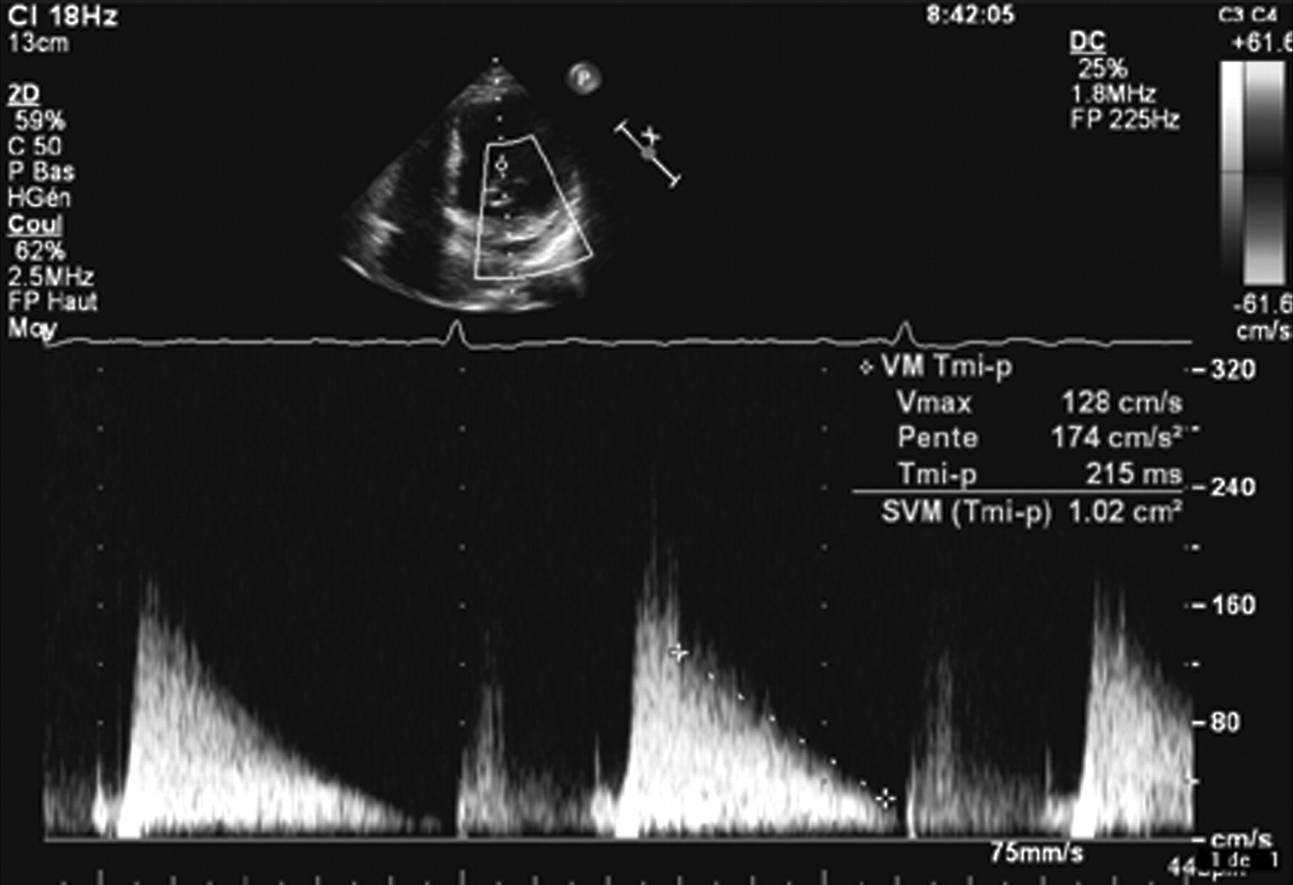

Estimation of mitral valve area using the pressure half-time method in a patient with mitral stenosis in atrial

fibrillation. Valve area is 1.02 cm2.